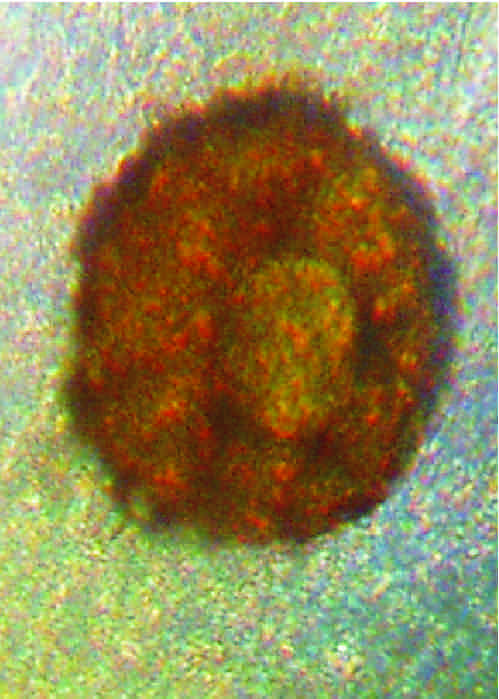

znalezione w odchodach - powiekszenie x120 i x500

(jest okragle, tylko na tych zdjeciach robi sie jajo)

Teraz o tym co (słabo

) widać. Na nr.1 to może być skorupka pełzaka - ameby. Na drugim - nie wiem (wydaje mi się zbyt symetryczny ten obiekt, żeby mógł być czymś, co nas może interesować

). Teoretycznie mógłby być niby jakąś cystą, niekoniecznie groźną, ale moim zdaniem jest zbyt symetryczny.

to sa fotki tego samego ustrojstwa w powiekszeniach x120 i x500,